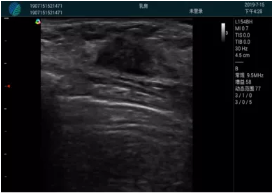

腺體內(nèi)部清晰顯示一低回聲塊影,形態(tài)不規(guī)則,邊界模糊,邊緣呈毛刺狀,內(nèi)部見砂礫樣鈣化

M20引導(dǎo)下穿刺活檢術(shù)

M20引導(dǎo)下平面內(nèi)穿刺取出的腫塊組織